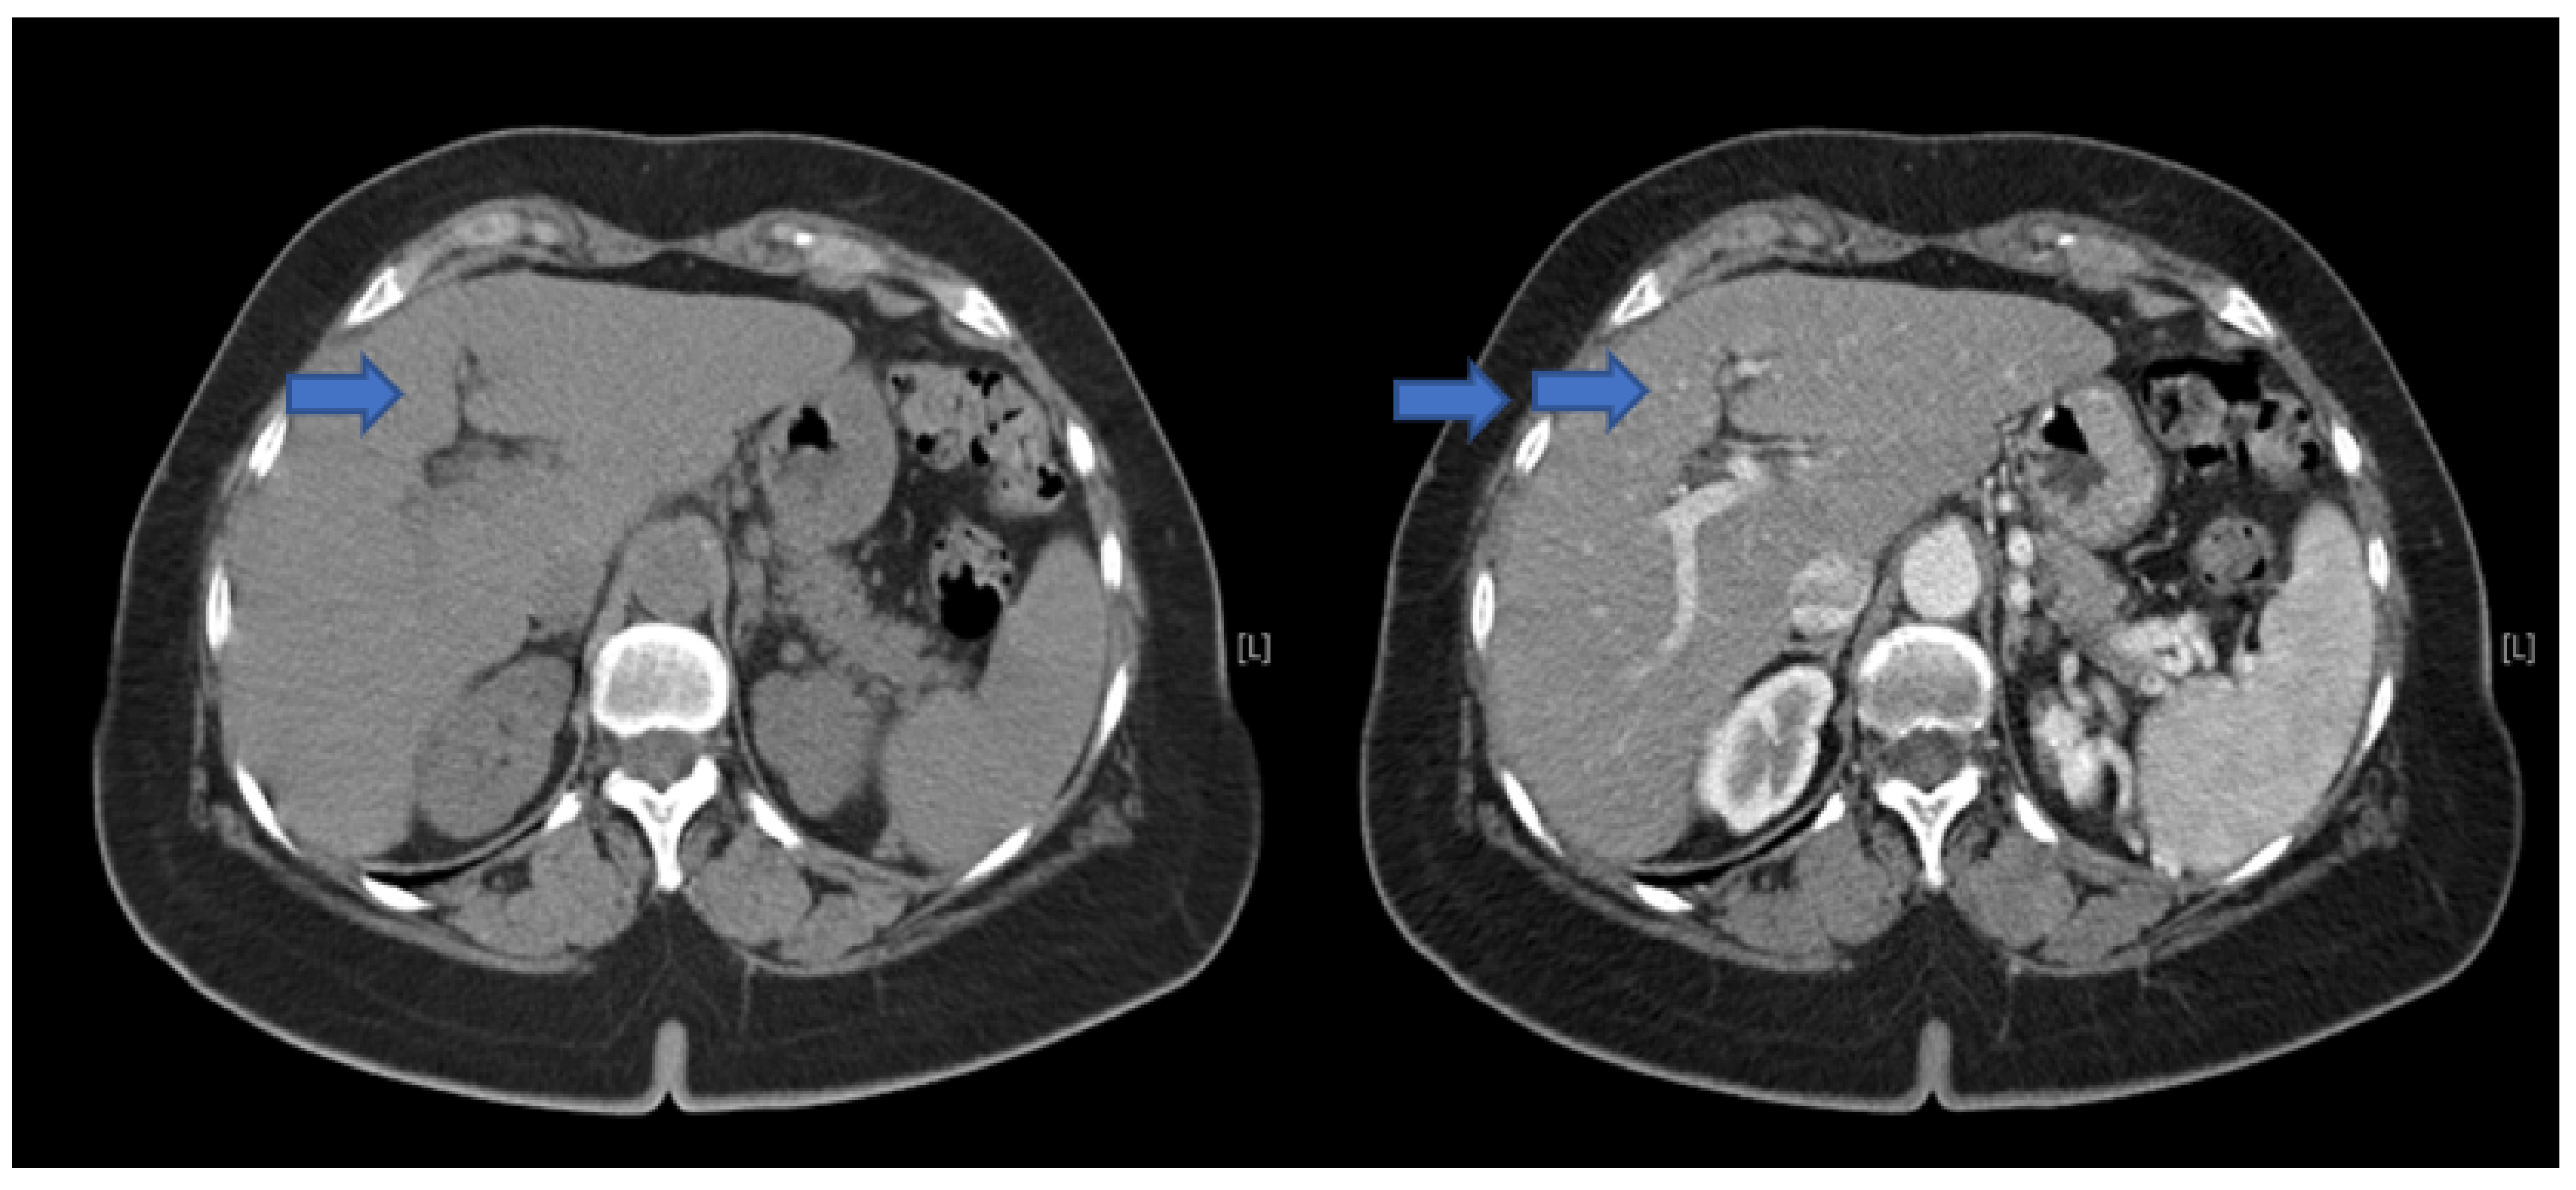

2. Case Presentation and Results